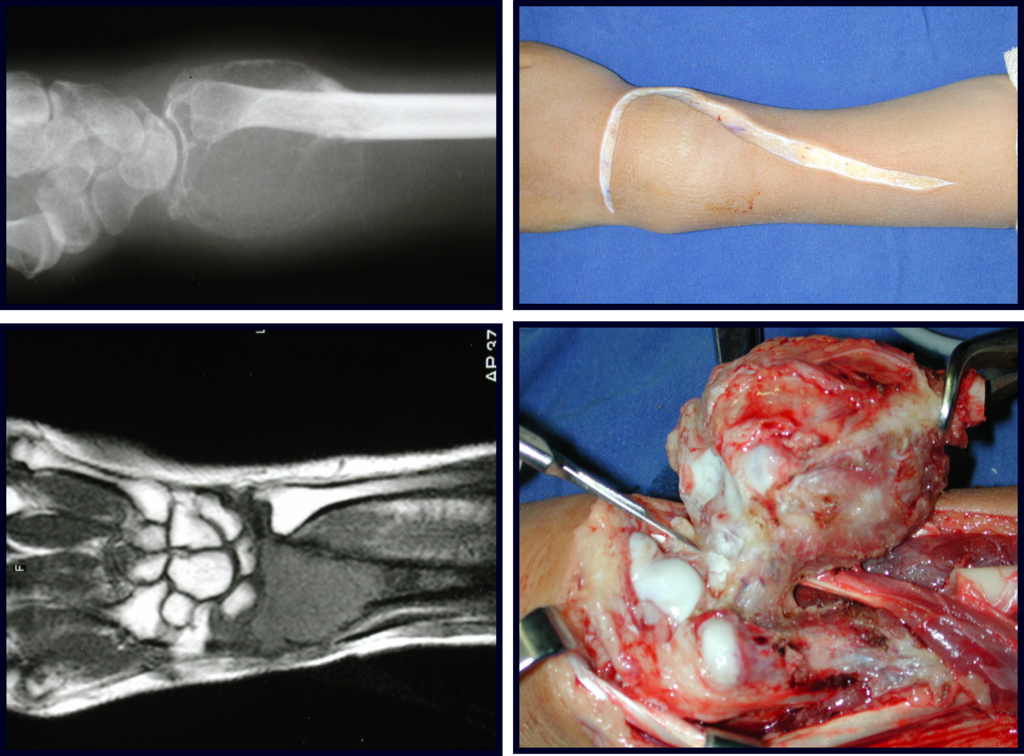

Cuando necesitamos una pequeña cantidad de injerto no cuestionamos mucho su indicación. A modo de ejemplo, en el caso de la necesidad de resecar los 3/4 proximales del radio, debido a una lesión tumoral, que pretendemos resolver realizando una “sinostosis” radiocubital distal, figuras 1 a 4.

Cuando necesitamos Reconstrucción con apertura de la sindesmosis radiocubital distal, interposición de un injerto óseo autólogo y fijación con dos tornillos Inter fragmentarios, figura 2.

Tres años después de realizar la sinostosis radiocubital distal, podemos verificar la consolidación, la integración total del injerto y observar que las fases de radio y cúbito continúan con crecimiento simétrico, con buena función, figuras 3 y 4.